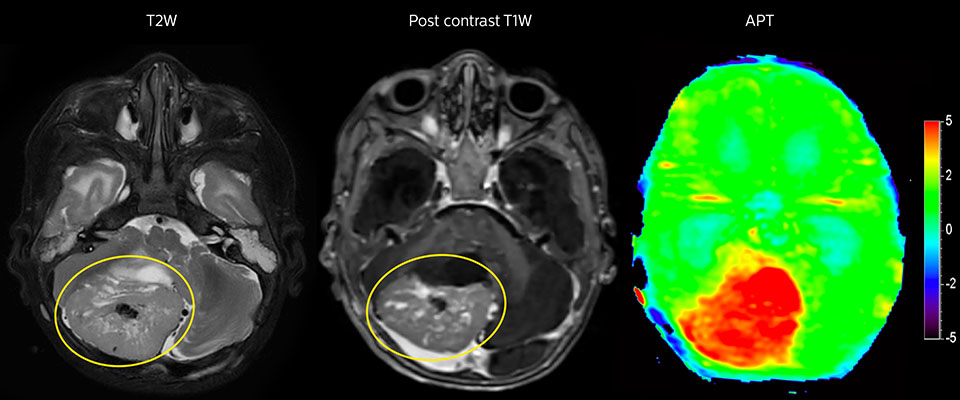

APT imaging of high-grade tumor

Tumor evaluation in a 1-year-old child with medulloblastoma. This aggressive tumor type is very solid and homogeneous. The high APT signal corresponds with the post-contrast image of this high-grade tumor.

Tumor grade and APT signal have been observed to be commonly positively correlated: high-grade tumors tend to exhibit a high APT contrast.[12-15] APT images can be seen to visualize tumor with more emphasis than post-contrast images, resulting in a scan that may be easier to interpret. Scientific studies comparing tumor grades with APT signal in adult glioma suggest that APT can support tumor grading, separating high-grade from low-grade, even when traditional MRI is inconclusive.[5,13,14]